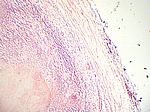

Käsige Lymphknoten-TBC, HE